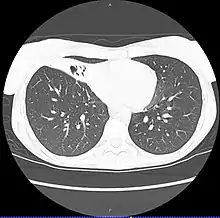

| CT scan of patient with right middle lobe aspiration and Mycobacterium avium infection consistent with Lady Windermere syndrome | |

MAC usually affects patients with abnormal lungs or bronchi. However, Jerome Reich and Richard Johnson describe a series of six patients with MAC infection of the right middle lobe or lingula who did not have any predisposing lung disorders.[17][18]

The right middle lobe and lingula of the lungs are served by bronchi that are oriented downward when a person is in the upright position. As a result, these areas of the lung may be more dependent upon vigorous voluntary expectoration (cough) for clearance of bacteria and secretions.

Since the six patients in their retrospective case series were older females, Reich and Johnson proposed that patients without a vigorous cough may develop right middle lobe or left lingular infection with MAC. They proposed this syndrome be named Lady Windermere syndrome, after the character Lady Windermere in Oscar Wilde's play Lady Windermere's Fan. However, little research has confirmed this speculative cause.[19]